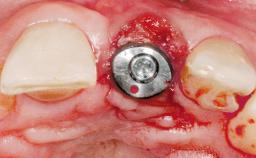

A 30-year-old female patient had lost tooth 21 and was referred to our clinic for consultation and treatment. Due to advanced apical infection, tooth 21 had been extracted two months earlier at another clinic and an acrylic-resin tooth had been bonded to the adjacent teeth. The patient desired implant treatment to avoid any damage to the adjacent natural teeth. While the patient had no history of any systemic disorder, she was a heavy smoker and exhibited medium to advanced periodontitis in the entire jaw. After the initial treatment to achieve a pocket probing depth of less than 4 mm and no bleeding on probing, a decrease in the height of the papillae mesial and distal to the extraction site and overall gingival recession were observed.

| Type of Implants | One-Piece|Reduced-Diameter |

| Bone Augmentation | Horizontal|Staged |

| Augmentation Materials | Autogenous chips|Membrane |